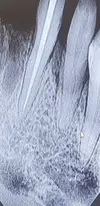

Toothache

Dental Caries

Tooth and Gum Diseases

Implant Treatment